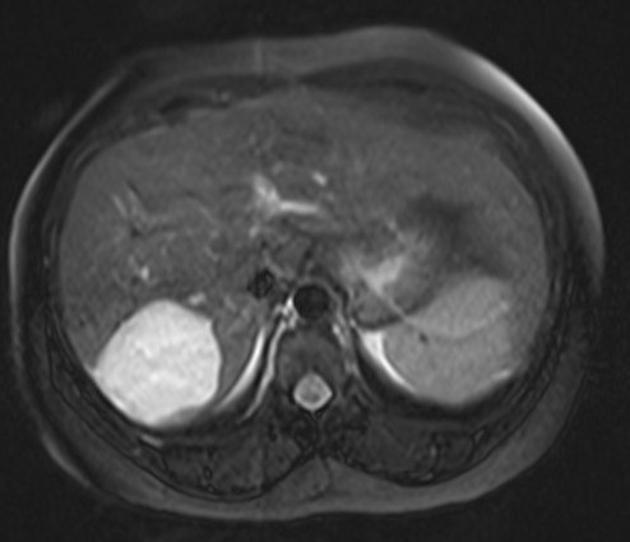

Tumores Benignos do Fígado: O Que Você Precisa Saber sobre hemangiomas, adenomas e hiperplasia nodular focal